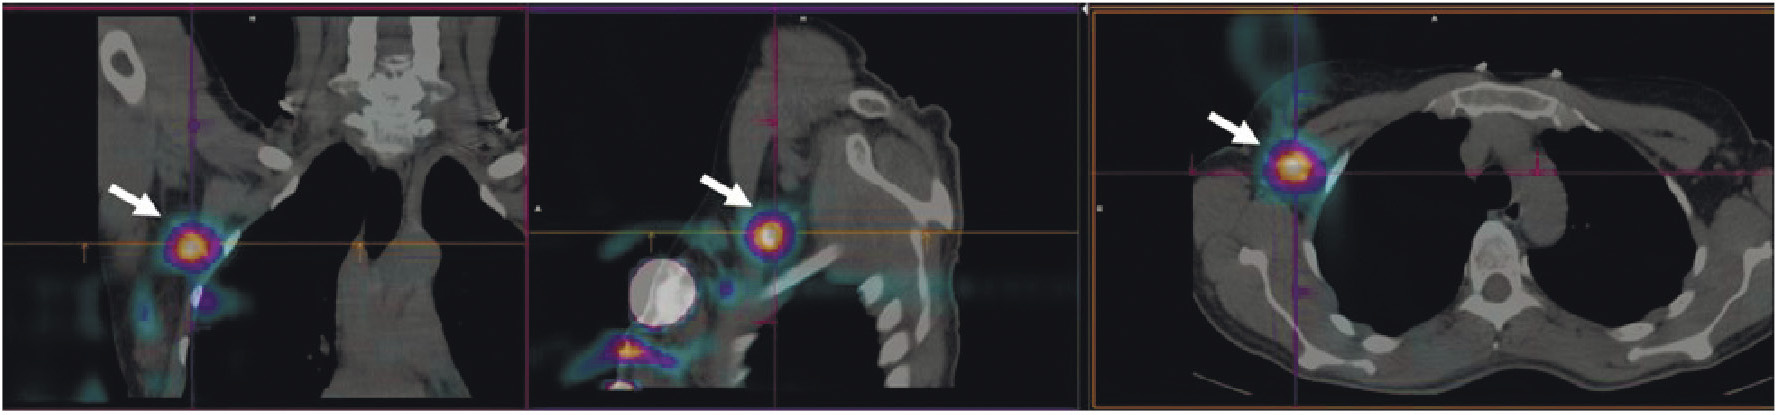

В мировой ядерной медицине для сцинтиграфии обычно применяют 111In-пентетреотид, или 111In-октреотид ([111In-DTPA]octreotide, OctreoScan, Tyco Healthcare, США; АО “Фармсинтез”, Россия). Основные показания к его использованию — стадирование, рестадирование и мониторинг лечения нейроэндокринных SSTR-позитивных опухолей. В последние годы 111In-пентетреотид служит для радионавигации при хирургическом лечении новообразований с гиперэкспрессией соматостатиновых рецепторов. К сожалению, физические характеристики индия-111 (длительный период полураспада, неоптимальный для регистрации на гамма-камере спектр излучения, высокая стоимость циклотронного производства) ограничивают его применение в радионуклидной диагностике. В связи с этим не подвергается сомнению актуальность создания в России меченного технецием-99м октреотида для ОФЭКТ-диагностики нейроэндокринных опухолей. Разработкой такого радиофармпрепарата в рамках проекта федеральной целевой программы “Фарма-2020” занимался ТПУ в сотрудничестве с НИИ онкологии Томского НИМЦ. Клинические испытания отечественного 99mТс-октреотида продемонстрировали его высокую эффективность при диагностике и стадировании НЭО (рис. 3). В настоящее время набор для приготовления этого РФЛП зарегистрирован в России под названием “Нейроскан, 99mТс”, а его производство налажено в ТПУ.

Рис. 3. ОФЭКТ/КТ с 99mТс-октреотидом пациента с нейроэндокринным раком лёгкого: а — конгломерат первичной опухоли и метастазов в лимфатические узлы; б — метастазы в кости; в – селезёнка

В рутинной клинической практике для ПЭТ/КТ-визуализации опухоли предстательной железы и её метастазов применяются радиофармпрепараты на основе простатспецифических мембранных антигенов, меченных 68Ga ([68Ga]Ga-ПСМА-11, [68Ga]Ga-ПСМА-617, [68Ga]Ga-ПСМА-I&T) либо 18F ([18F]F-DCFPyL, [18F]F-ПСМА-1007) [22, 23]. Главные преимущества меченных 99mТс препаратов, тропных к ПСМА, — невысокая стоимость и доступность технеция-99m, а также возможность визуализации опухоли с помощью гамма-камеры. В настоящее время для этих целей предложен ряд радиофармпрепаратов [24]. В России зарегистрированы наборы для приготовления 99mTc-HYNIC-ПСМА (“ПСМА HYNIC, 99mТс”, Польша; “Проскан, 99mТс”, Россия). Отечественный РФЛП разрабатывался в ТПУ и НИИ онкологии Томского НИМЦ. Клинические испытания 99mТс-ПСМА показали его высокую эффективность при диагностике и стадировании рака простаты, а также при отборе на радиолигандную терапию и оценке её воздействия (рис. 4).

Рис. 4. ОФЭКТ с 99mТс-ПСМА пациента с раком простаты до (а) и после (б) четырёх курсов радиолигандной терапии 177Lu-ПСМА